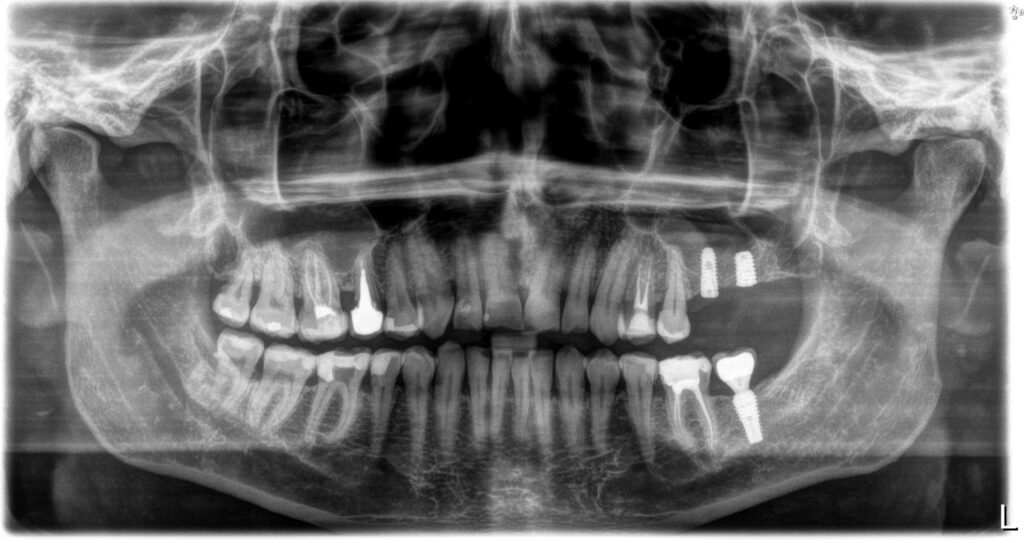

Implantologia to dziedzina stomatologii, która zajmuje się odbudową utraconych zębów za pomocą implantów zębowych. W praktyce implanty to małe, tytanowe śruby, które zastępują korzenie zębów i stanowią podstawę do założenia koron, mostów lub protez. W Szczygieł Stomatologia dbamy o to, aby każdy etap leczenia był dopracowany do perfekcji.

Współpraca z doświadczonym specjalistą, jakim jest nasz implantolog Białystok, daje pacjentom gwarancję najwyższej jakości usług i trwałych efektów. Procedura leczenia implantologicznego składa się z kilku etapów, wśród których znajdują się konsultacja, wszczepienie implantu, okres gojenia oraz założenie uzupełnienia protetycznego. Każdy przypadek traktujemy indywidualnie, by sprostać potrzebom i oczekiwaniom pacjenta.

Korony to uzupełnienia protetyczne, które odtwarzają naturalny wygląd i funkcję uszkodzonych zębów. Są zakładane na oszlifowane zęby lub implanty, stanowiąc estetyczne i wytrzymałe rozwiązanie. W naszym gabinecie stosujemy nowoczesne materiały, dzięki czemu korony cechuje niezwykła trwałość oraz naturalny wygląd.